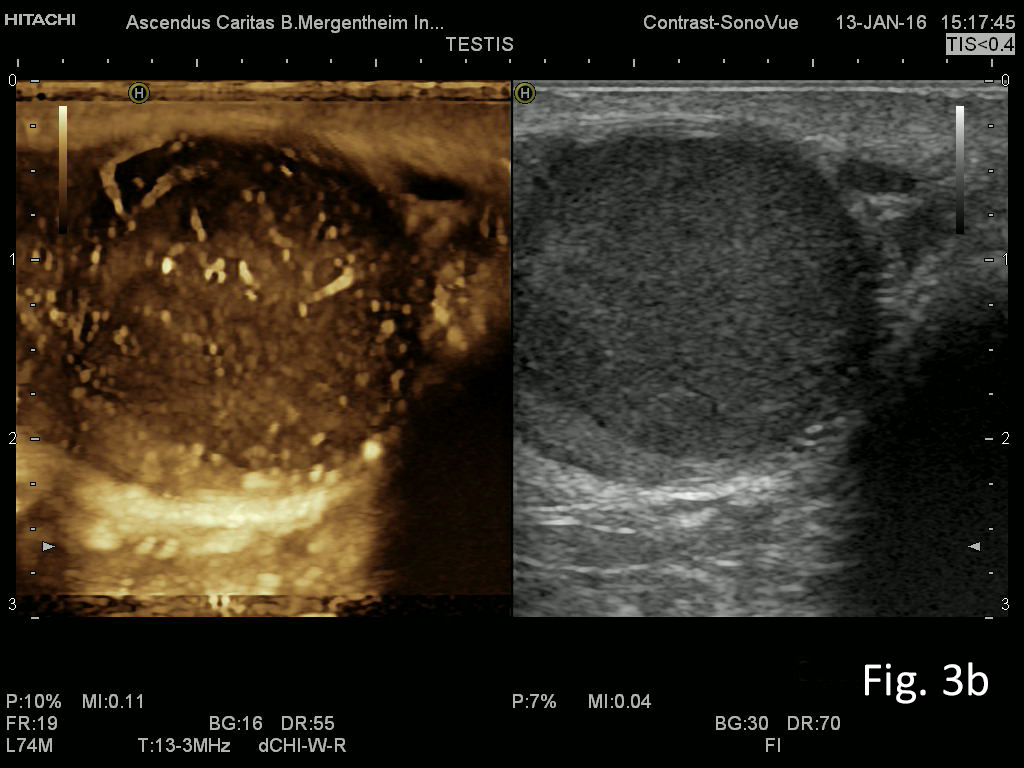

We report on a 28 year old male presenting with unspecific abdominal pain for two weeks. B-mode ultrasound revealed extended abdominal lymphadenopathy [Figure 1] and two small unspectacular hemangioma-like focal liver lesions [Figure 2]. The left testis revealed a palpable tumour by ultrasound also examined with elastography and contrast enhanced ultrasound [Figure 3 and 4]. Endoscopy of the upper gastrointestinal tract showed candida of the esophagus. The biopsy of the abdominal (retroperitoneal) lymph nodes revealed epithelial cells, typical for testicular embryonal cell carcinoma.

Figure 3: Imaging of the left testicle using elastography with sharp delineation of the embryonal cell carcinoma with clear stiffer elastographic delineation from the surrounding tissue (a) and CEUS with atypical neoplastic vessels and little perfusion (b).